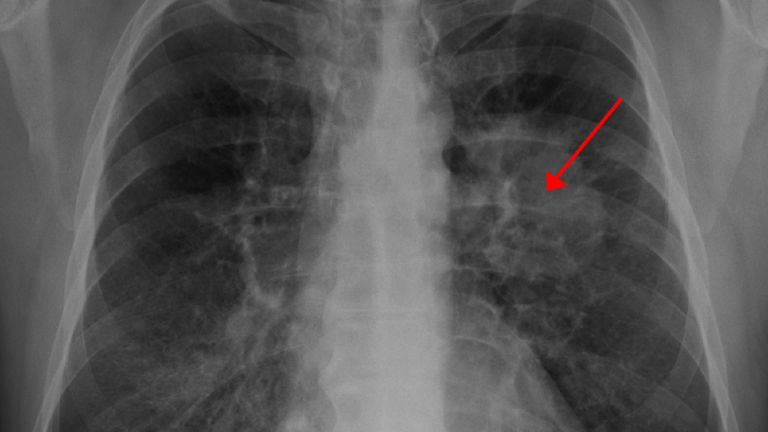

V Evropi zaradi onesnaženosti zraka vsako leto predčasno umre kar 400.000 ljudi. Onesnažen zrak namreč škoduje našemu zdravju in povzroča številne bolezni.

Cestni promet, ki onesnažuje zrak v naših mestih, ne škoduje le okolju, močno vpliva tudi na zdravje prebivalcev. Na Nacionalnem inštitutu za javno zdravje pojasnjujejo, da onesnaženost zraka povzroča prezgodnjo umrljivost, razvoj bolezni srca in ožilja, pljučnega raka, sladkorno bolezen in astmo. ''Kljub številnim ukrepom v Evropi zaradi onesnaženosti zraka vsako leto predčasno umre kar 400.000 ljudi. Slab zrak še posebej prizadene otroke in starejše,'' povedo na inštitutu, kjer si prizadevajo osveščati ljudi o pomenu spreminjanja potovalnih navad in spodbujanju rabe novih, čistejših tehnologij.